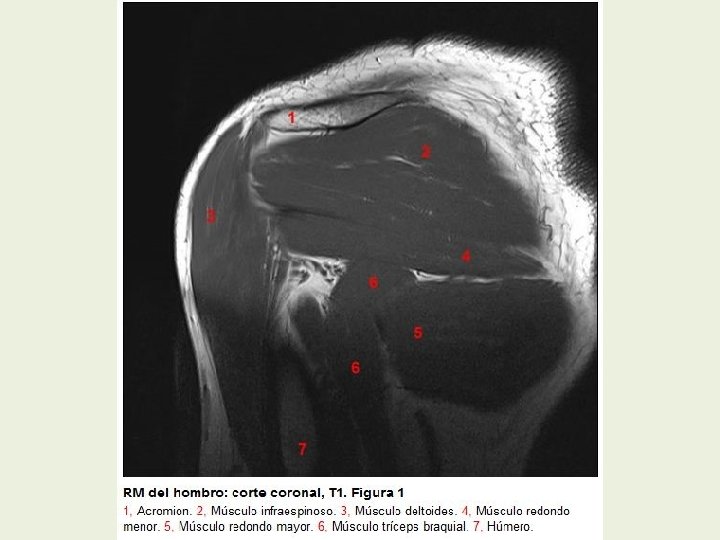

Hombro Cortes coronales RMN